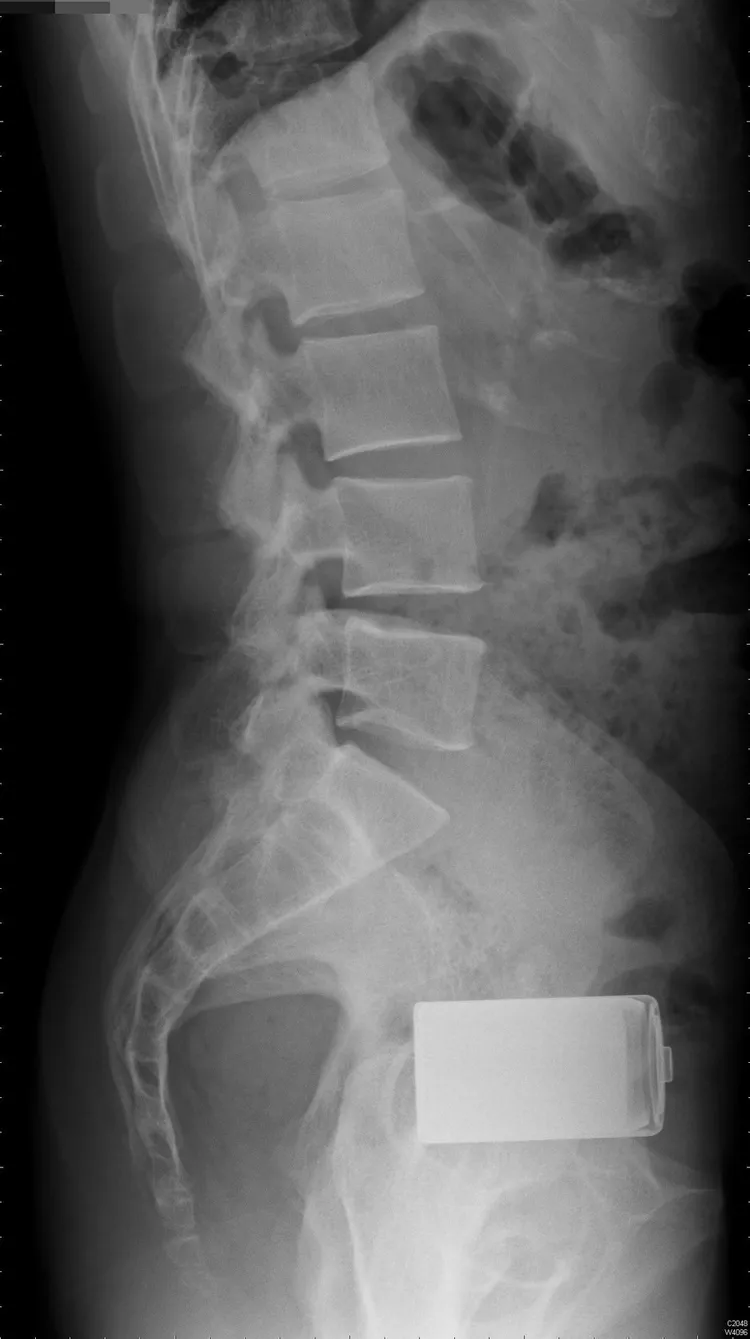

收治男子的高雄長庚醫院大腸直腸外科主治醫師蔡鎧隆表示,男子走進急診室自述剛與朋友喝酒,朋友塞了顆電池到他的肛門,醫護隨即為他安排X光檢查,一顆一號的大電池就在男子的肛門裡。

蔡鎧隆接著戴上手套,但不管是徒手或以內視鏡伸進,都因男子太緊張,肛門括約肌收縮,電池一再在男子體內滑掉,拿不出來,因此,他決定在開刀房裡,讓男子在全身麻醉下,再取出這顆電池。

男子以為電池拿出來了,可躲過開刀,可是男子肚子卻愈來愈痛,還狂冒冷汗,此時男子才說,剛才在廁所裡,其實是拿工具間裡的掃把,把掃把柄插進肛門裡「抐」電池,在一陣如「穿腸」般劇痛後,電池才「抐」了出來;蔡鎧隆研判男子腸子被「喇」破了,因此,還是推男子進開刀房。

蔡鎧隆說,為仔細檢查男子腸道破裂的位置,他在男子腹部劃開20公分刀口,果真發現直腸有個破洞,經切除約10公分被桶爛的這段腸子,再重新縫合,但男子術後仍因嚴重感染,引發腹膜炎,一度命危,住院一個月,持續使用抗生素,才化險為夷、康復出院。